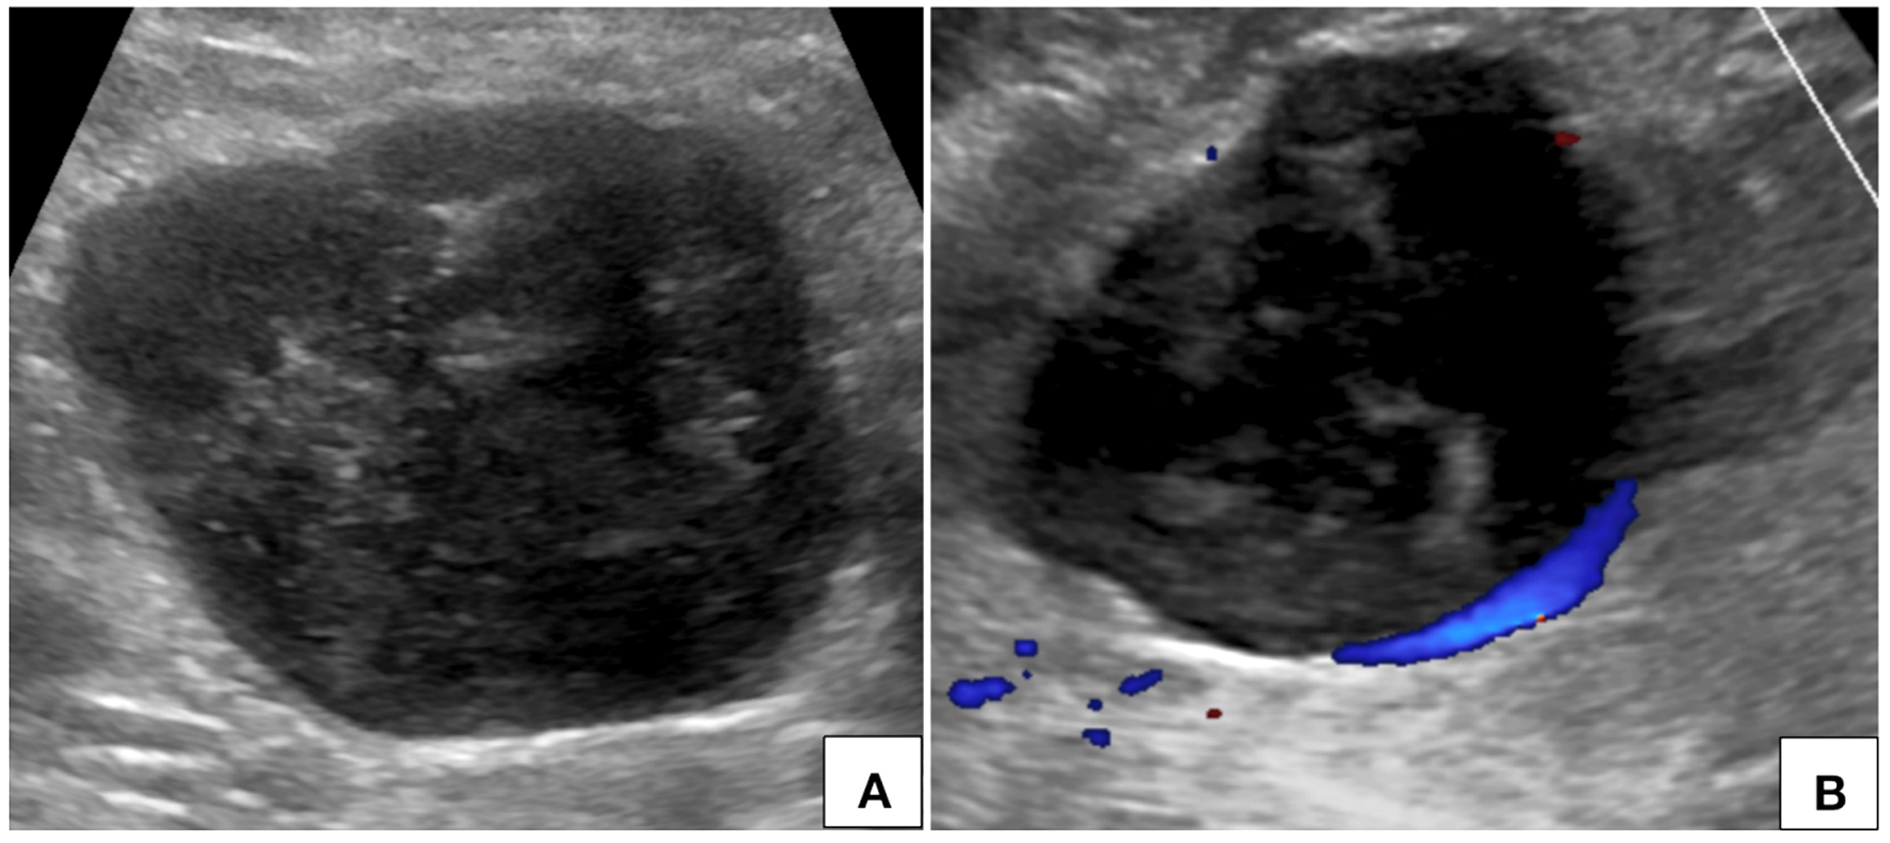

Routine ultrasonographic examination revealed a circumscribed hypoechoic lesion in the upper abdomen measuring 6.6 × 6.3 × 5.9 cm (CC × AP × Tr). For further evaluation, patient underwent computed tomography which revealed a circumscribed retroperitoneal soft tissue lesion in right side of midline, measuring 7.3 × 7.5 × 8.1cm (CC × AP × Tr). The lesion showed inhomogeneous contrast uptake on arterial phase and homogeneous enhancement on portal venous and delayed phases with few nonenhancing areas within. It was abutting the inferior vena cava posteriorly with imperceptible

lumen at the site of maximum contact. However, proximal and distal segments of the inferior vena cava showed normal contrast opacification. Medially, the lesion was in relation to the abdominal aorta. Second and third part of duodenum and head of pancreas were displaced anterosuperiorly. Magnetic resonance imaging (MRI) showed a homogeneously enhancing circumscribed lesion in the retroperitoneum on right side of midline appearing isointense on T1W, hyperintense on T2W showing restricted diffusion. Few cystic areas were seen within the lesion. On prone imaging, the lumen of inferior vena cava was still imperceptible at the site of maximum contact. No obvious intraluminal extension was seen. Whole body positron emission tomography CT revealed mild FDG uptake with a maximum standard uptake value (SUVmax) of 4.1. No distant metastases were found.